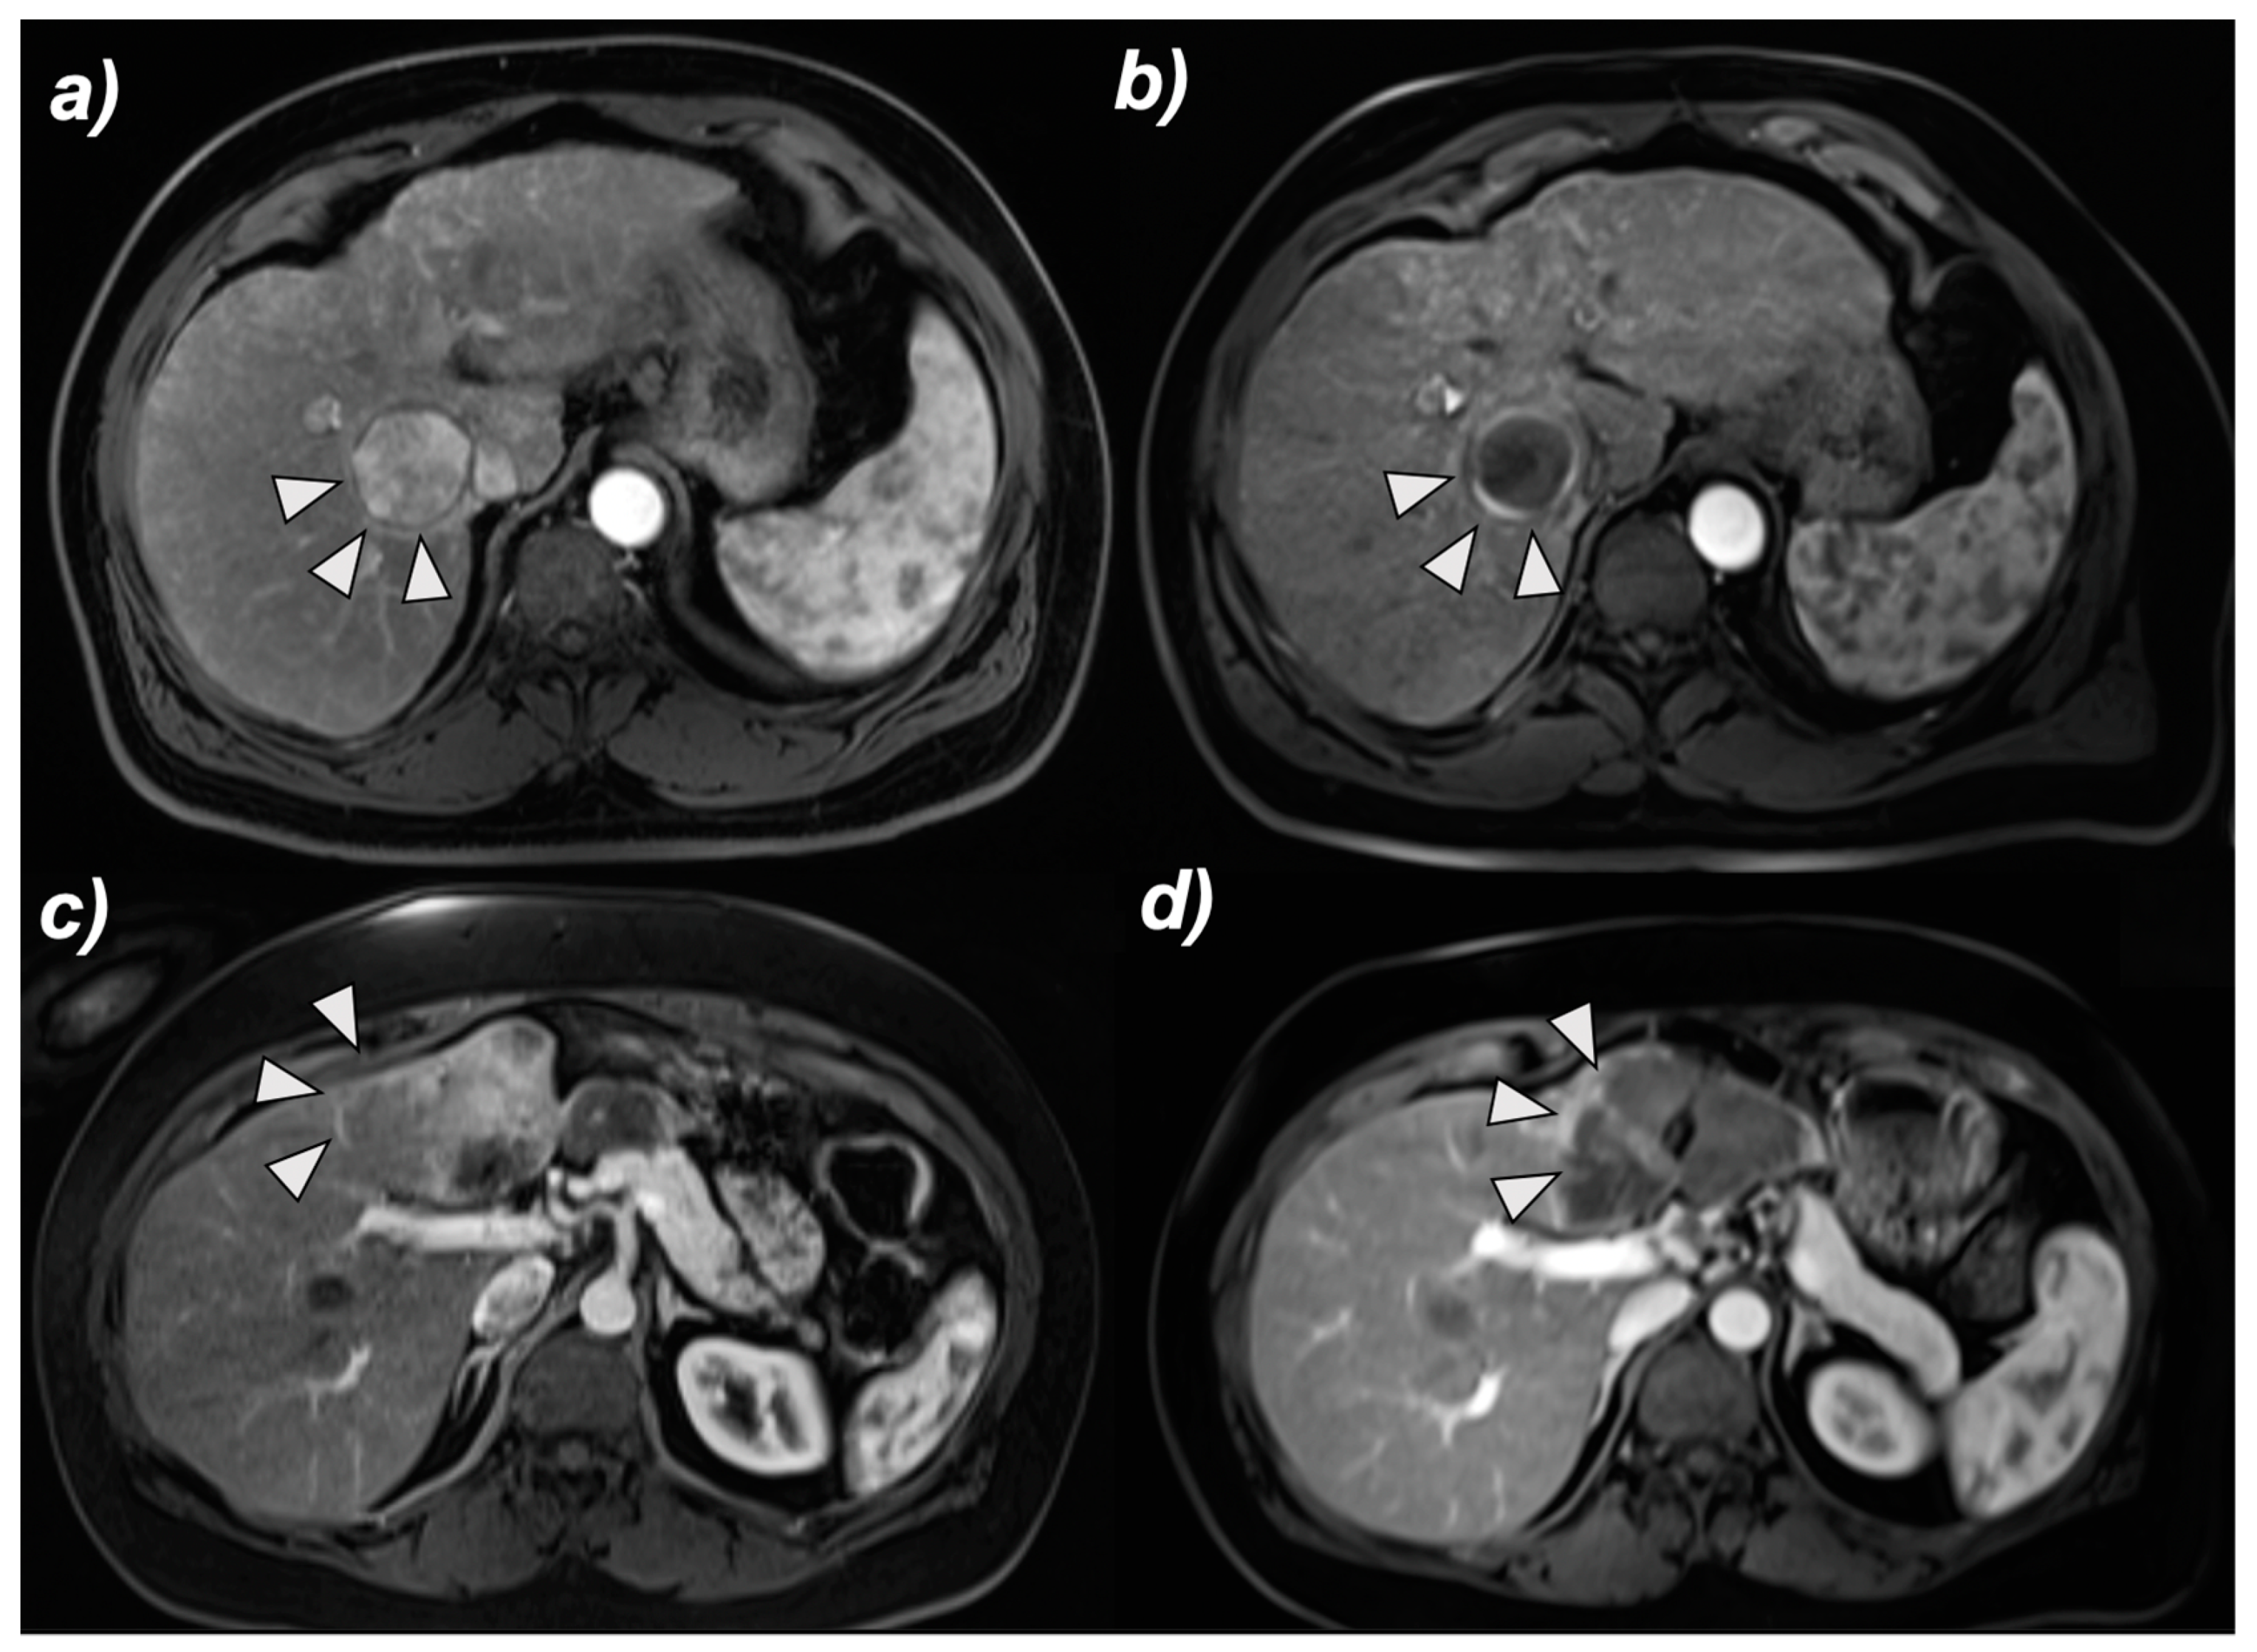

2.3. MRI and Image Analysis